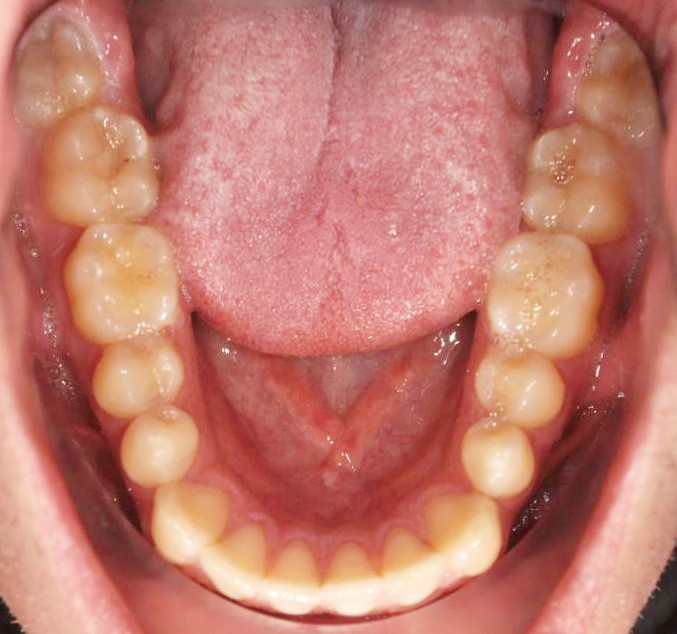

En intra-arcades (fig. 4-6), on note une classe III molaire et canine (fig. 4-5), trois plans d’occlusion, une déviation des milieux d’origine mandibulaire et un inversé articulé du bloc incisif maxillaire ; le biotype parodontal est fin, et l’on note des récessions gingivales (12, 13, 23, 33, 43) certainement dues à la mauvaise position et aux forces mal réparties lors de la mastication (fig. 5). L’arcade maxillaire est carrée avec une DDM antérieure (fig. 7), l’arcade mandibulaire étroite et allongée (fig. 8).